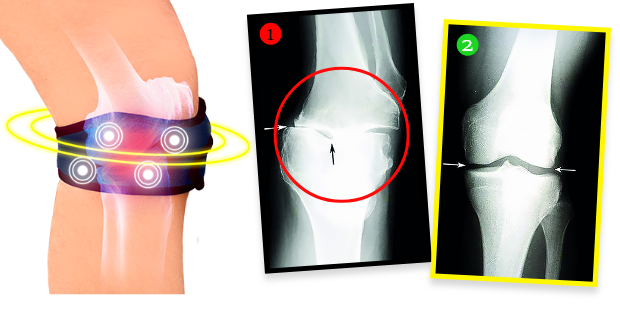

4 FAZY DZIAŁANIA biomagnetycznej opaski przeciwbólowo-regeneracyjnej:

- Eliminuje ból i sztywność stawów już nawet w ciągu pierwszych 72 h noszenia

- Odciąża i stabilizuje stawy, przyspieszając procesy regeneracji chrząstek i odnowy mazi stawowej

- Zmniejsza napięcie mięśni, regeneruje tkanki i wzmacnia struktury stawowe od wewnątrz, cofając zmiany zwyrodnieniowe

- Wygasza obrzęki i stany zapalne, trwale likwidując źródło bólu

Pani Helena zrobiła po kuracji badanie RTG i okazało się, że zmiany zwyrodnieniowe w kolanie całkowicie się cofnęły! Lekarz osłupiał – nie wiedział, co powiedzieć. A fakty są takie, że dzięki biomagnetycznej opasce stan kolana pani Heleny nie tylko przestał się pogarszać. Tkanka chrzęstna i delikatne struktury w obrębie stawu zregenerowały się, a kolano wróciło do całkowitej sprawności sprzed lat. Opaska emituje bowiem naturalne i bezpieczne pole biomagnetyczne, które przenika w najgłębsze tkanki stawu, odżywiając i regenerując chrząstkę, przywracając jej elastyczność i sprężystość, a także stymuluje produkcję mazi stawowej, która amortyzuje i chroni przed bolesnym tarciem podczas poruszania się. Jest to terapia w pełni bezinwazyjna i bezpieczna.